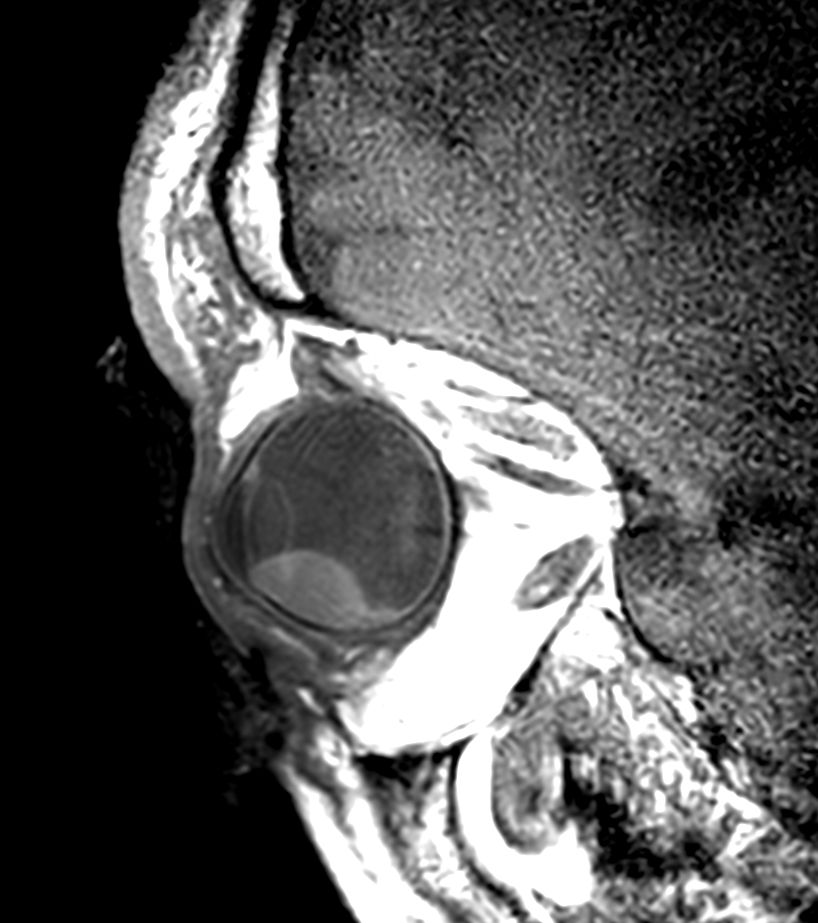

4 different 3D isotropic sequences, T1W with and without fat saturation, T2W and T1W fat saturation post-contrast are used to evaluate the tumor prior to treatment. Isotropic sequences are used to allow for good quality multiplanar reconstruction corresponding to the location of the tumor; as the tumor can be located anywhere in the eye, optimal visualization often requires an assessment of different oblique planes, which is facilitated by the 3D isotropic sequences. The pre-contrast sequences help evaluate the tumor size and location and the post-contrast sequence provides additional information such as identifying tumor that has seeped through the sclera behind the eye and differentiating tumor vs associated retinal detachment.

Higher in-plane resolution 2D sequences are used to better evaluate the tumor and screen for infiltration to the adjacent structures, which can have direct therapeutic consequences.